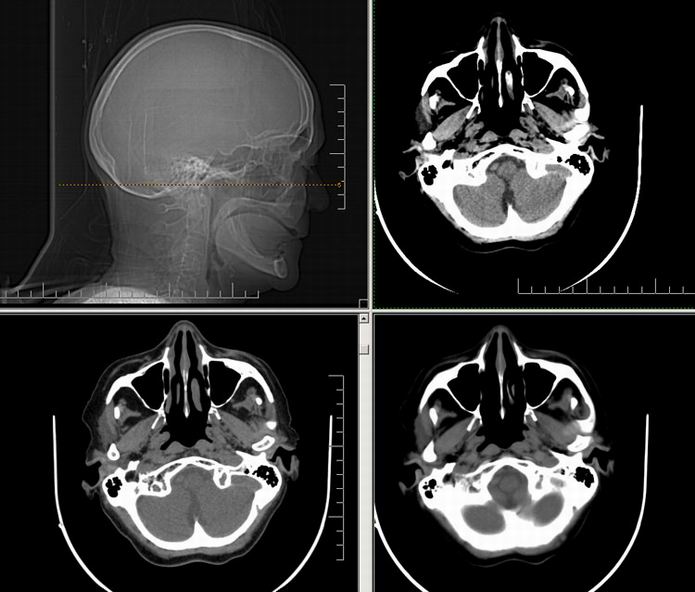

Est ce que qqun a des coupes axiales de crâne pour m'aider à réviser mon anatomie. Merci

Pour compléter tes révisions, Poupette vient de nous faire parvenir ces planches bien utiles: Planches de coupes axiales cérébrales, dans la rubrique COURS / ANATOMIE